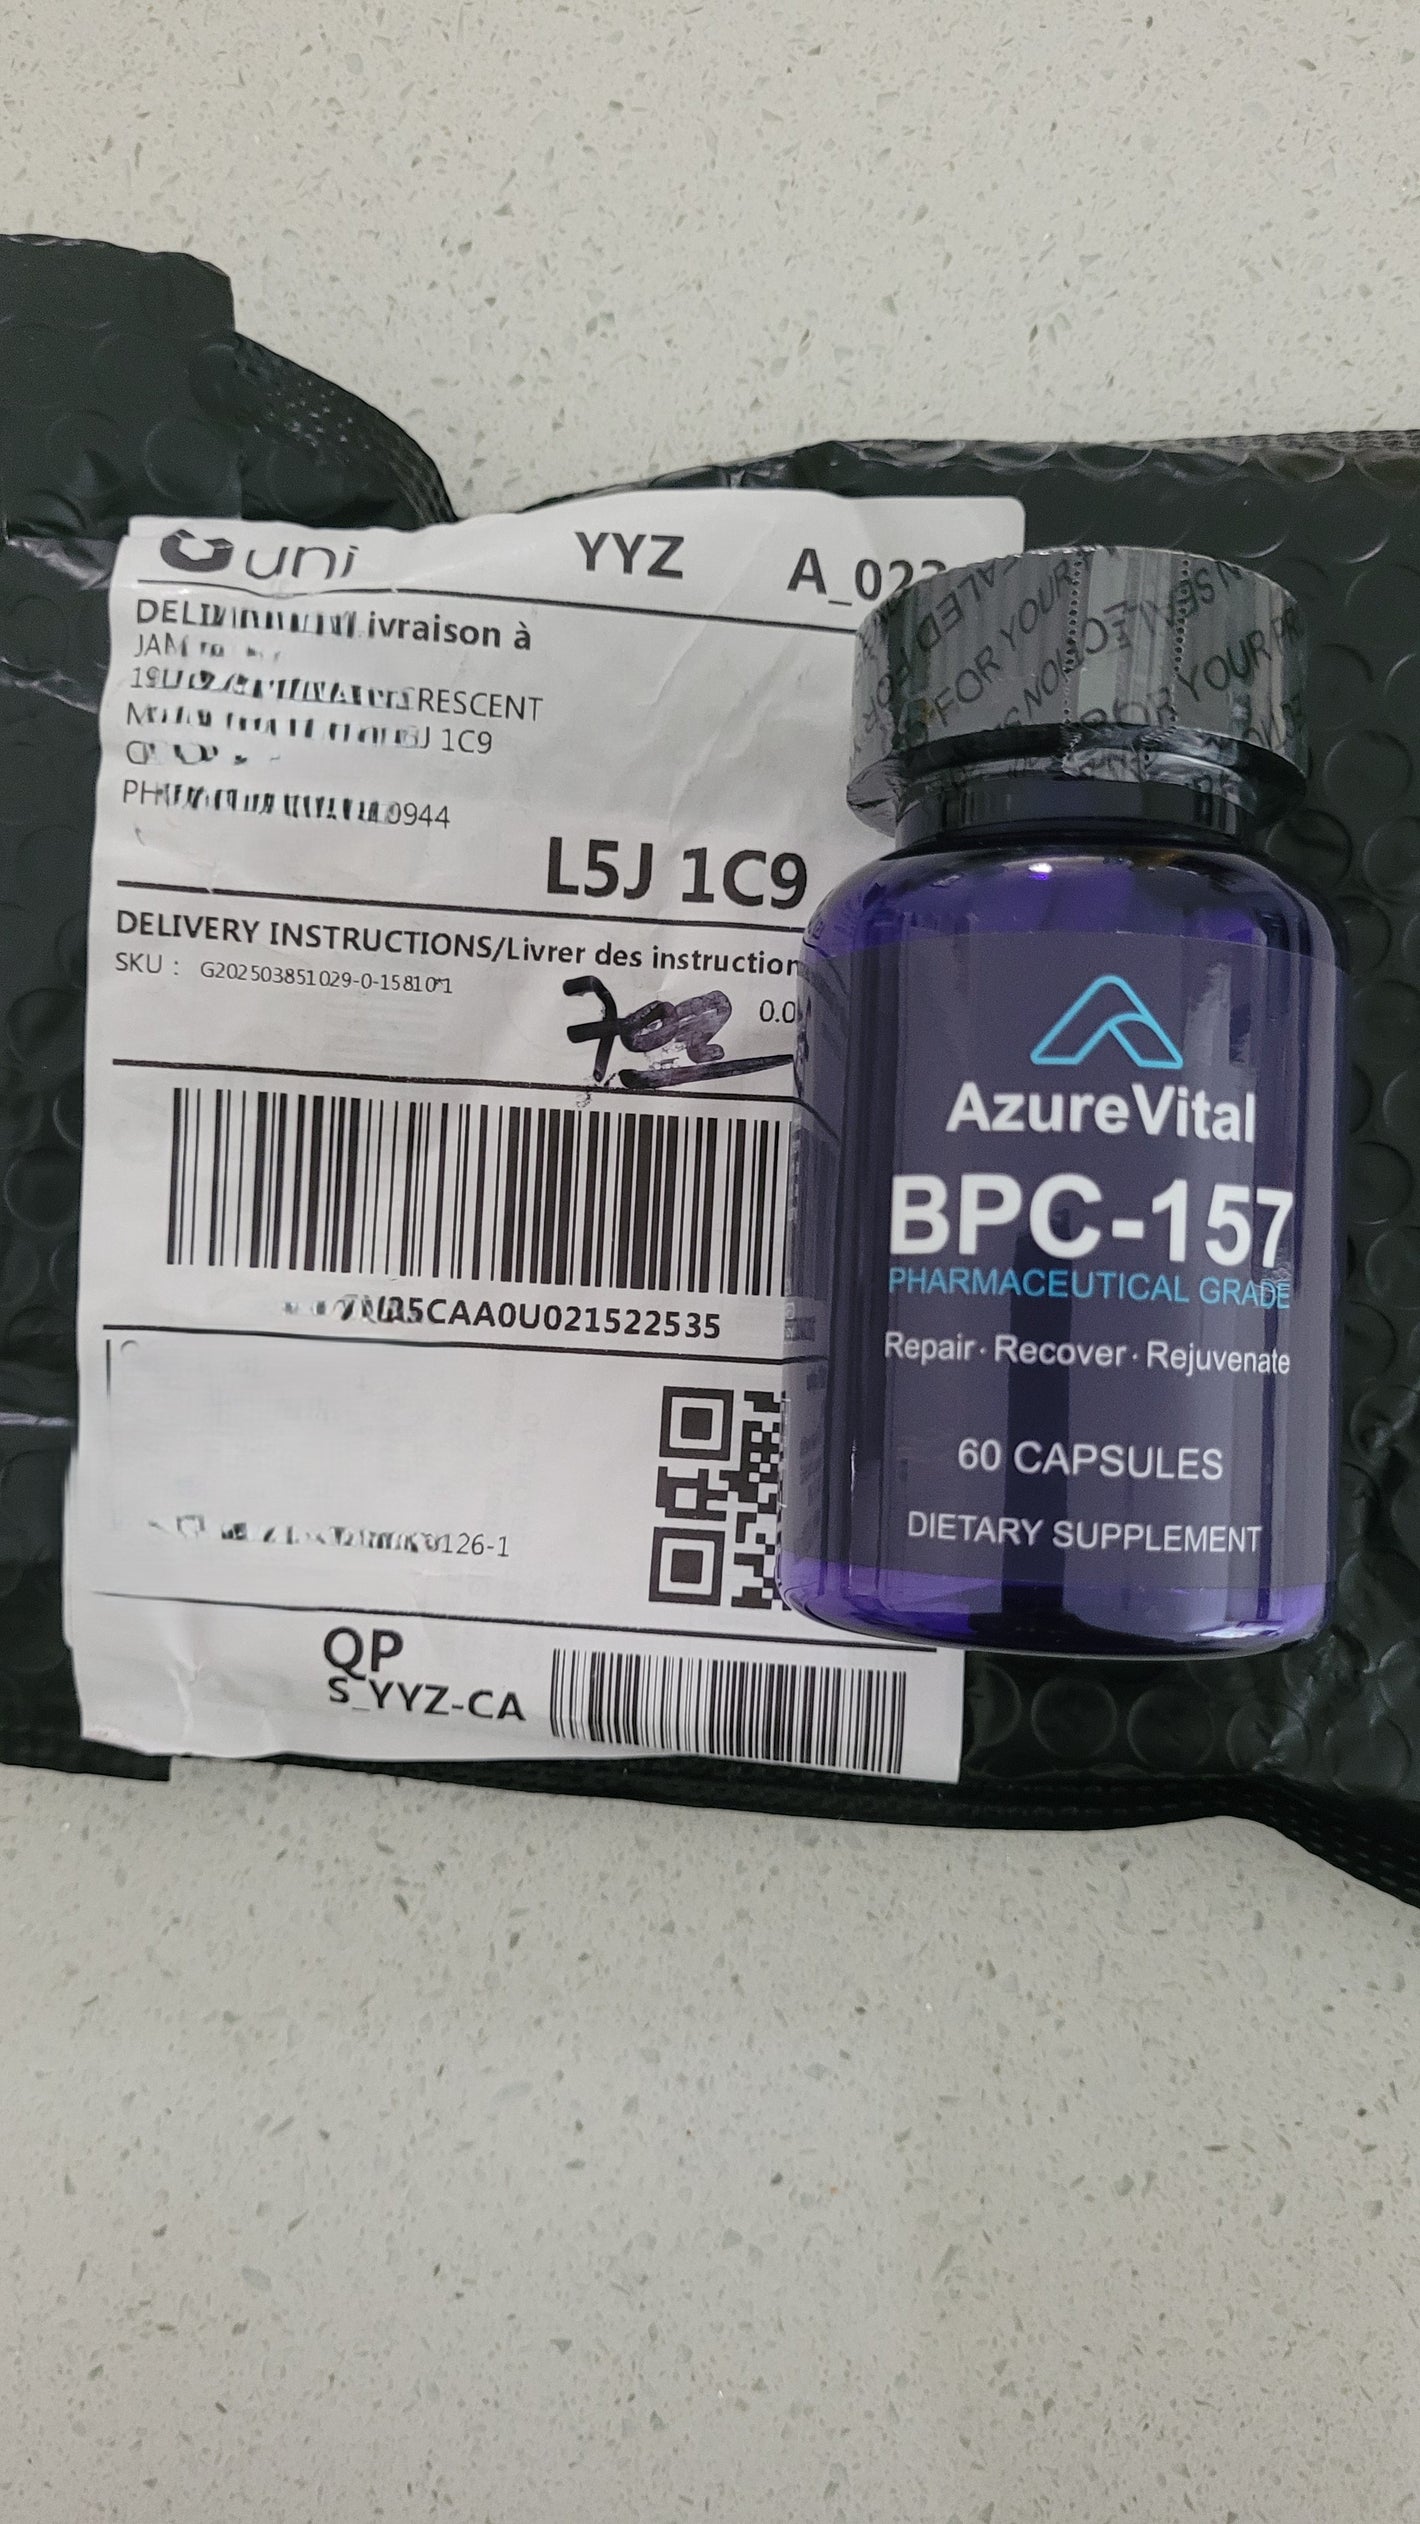

2. What are the ingredients in BPC-157?

2. What are the ingredients in BPC-157?

Each serving contains 1000mcg of BPC-157 , which includes amino acids such as L-Valine, L-Glutamine, L-Glycine, L-Proline, L-Lysine, and others. The capsule is made from vegetable cellulose, and the formula is vegan, non-GMO, sugar-free, and dairy-free.

6. How do I know I’m getting real BPC-157?

6. How do I know I’m getting real BPC-157?

We prioritize transparency and quality. Our BPC-157 is manufactured in certified facilities, and each batch is tested for purity and identity to ensure you're getting the real, active ingredient — not a diluted or mislabeled product.